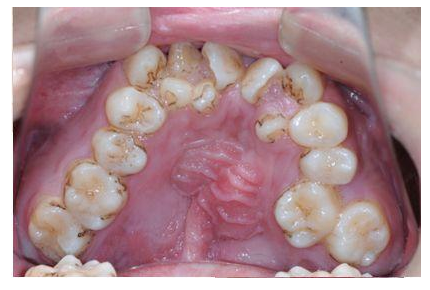

误区1:牙齿不齐只影响美观并无大碍

牙齿畸形不仅影响美观,还可能会影响口腔功能的正常发挥,如咀嚼功能、发音功能、呼吸功能,甚至由于牙齿排列不齐,难以清洁导致蛀牙等。

对于青少年阶段的牙齿畸形问题,应该及时选择适宜的早期矫治,才能更好地促进儿童面部和牙弓的发育,为现有牙齿和即将萌出的恒牙创造空间。